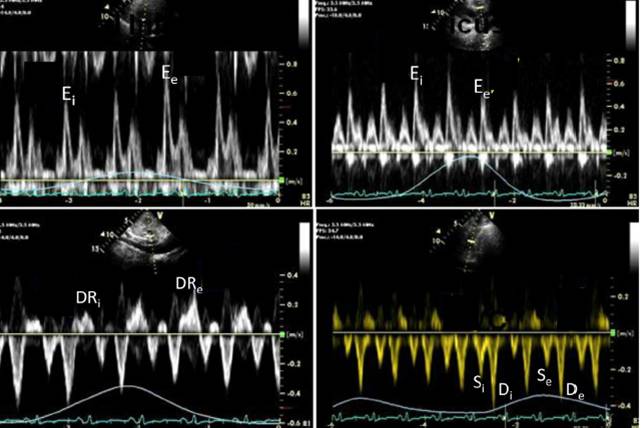

缩窄性心包炎与限制性心肌病的主要鉴别点

M型:室间隔运动随呼吸变化 typical CP

缩窄性心包炎,多普勒血流频谱

组织多普勒e’

缩窄性心包炎

类风关,缩窄